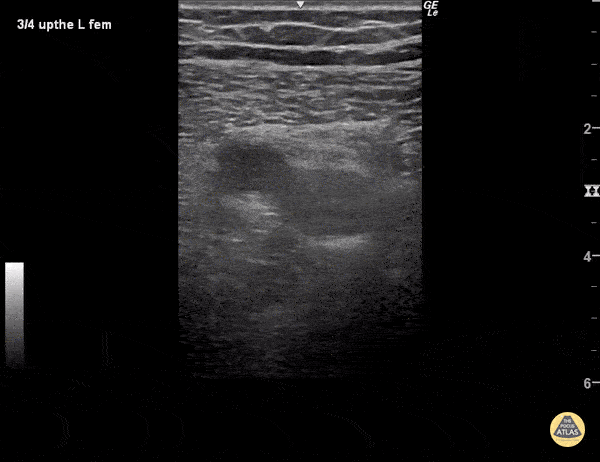

The superficial femoral artery (pulsatile, to the left) and superficial femoral vein are visualized. As pressure is applied to the probe, the artery becomes oblong but the vein does not collapse as it should, indicated a deep vein thrombosis within its walls. Veins should collapse before arteries under pressure as they have much thinner walls. Sukh Singh, MD